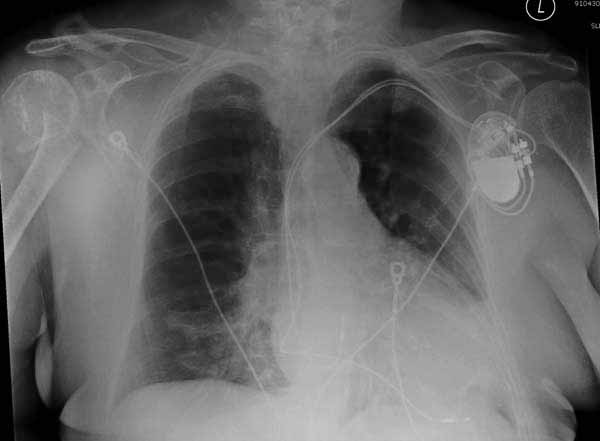

Уважаемы коллеги! Прошу помочь определиться с тактикой лечения пациентки. В феврале в отделение поступила пациентка с оскольчатым переломо-вывихом головки плечевой кости. Выполнена операция -остеосинтез блокируемой пластиной. Костная пластика не производилась. На контрольных рентгенограммах остается сублюксация головки и смещение большого бугорка. Интраоперационно бугорок подшивался с помощью лавсановых нитей. Послеоперационно: ношение косыночной повязки и пассивные движения в плечевом суставе в течение 2,5-х месяцев без особенностей. Через 2,5 месяца при попытке выполнения пассивно-активных движений произошел передний вывих плечевой кости.Вся реабилитация производилась по месту жительства. Таким образом существование вывиха в течение 1 месяца. Боли не беспокоят. Нейрососудистых нарушений в конечности нет. Что вы можете посоветовать: пластику, эндопротез, артродез? Заранее спасибо.

мне кажется ,что на послеоперационном снимке, также имеется сублюксация головки.сколько годов пациентке?

Набор мелких снимков не отражает истинную картину суставной поверхности лопатки, а также качество репозиции головки плеча. Необходимо доказать аксиальным снимком наличие покрытия головки. Правильная маркировка на рентген снимках и соответствие с выставленным диагнозом гарантирует от ошибок со стороной во время операции!

Здесь результат похожего случая, больная 87 лет, отягощенная сердечными делами и два года назад установка pacemaker и нескольких стентов. На третий день, сегодня утром сделали операцию. Послеоперационный псевдовывих связанный с релаксацией мышц и общим обезболиванием.